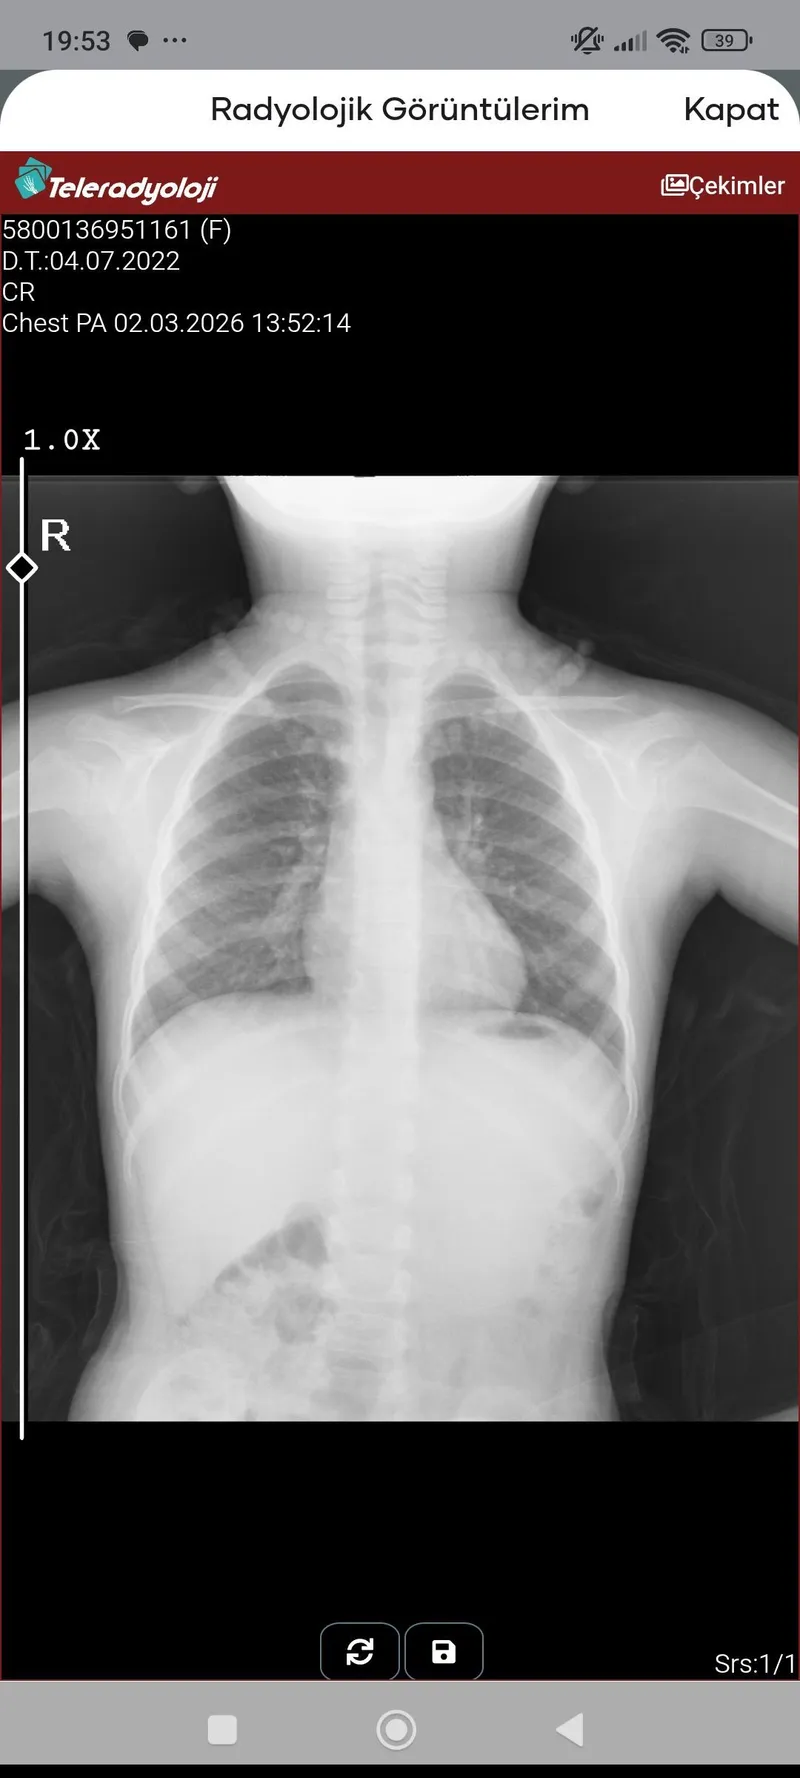

Merhaba Osman bey, pazar günü öksürük+ateş ile hastalık belirtisi başladı.( İki kere -38.6 ve 39.1 ateşlendi calpol ve dolven ile düşürdük). Pazartesi günü polikliniğe götürdük röntgen de yoğun balgam çıktı test yapılmadı ama RSV pozitif biri ile temasikiz olduğu için ventolin cortair ve klamer yazdı doktorumuzm. Aynı zamanda sizin videonuza denk geldim buharla sadece serum suyu verip masaj yapıyorum ve burnunu açıyorum. Merak ettiğim hava veya masaj sonrası gözle görülür balgam çıkışı olmuyor olması gerekir mi yoksa amaç yumuşatmak mı yanlış eksik yaptığımız birşey mi var acaba. Akciğer filmi bu şekilde.